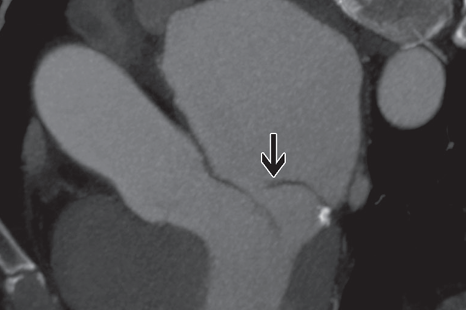

CT

- Image en “Fishmouth” sur restriction d’ouverture de la valve

- Epaississements, Calcifications

Stenose Mitrale

Epaississement des feuillets, sténose sur RAA

Epaississement des feuillets, sténose sur RAA